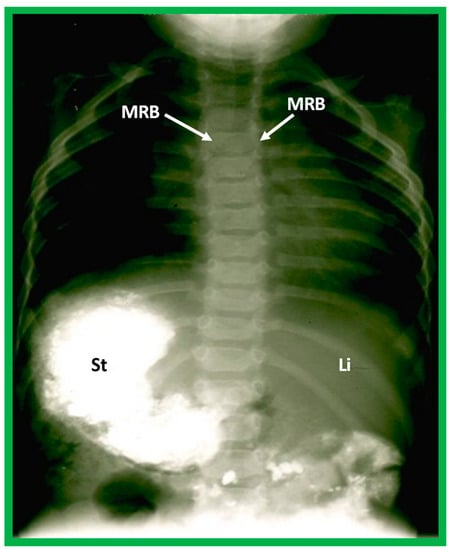

Figure 21. Barium study showing barium in the stomach (St) on the right side while the liver (Li) is seen on the left, indicating situs inversus. The heart is on the left side, indicating isolated levocardia. Tracheobronchial tree pattern shows morphologic right bronchus (MRB) on both sides, indicative of dextro-isomerism.

5.2.3. Tracheobronchial Tree Pattern

In typical patients with situs solitus, the bronchus on the right side is short and wide and descends somewhat steeply, whereas the bronchus on the left side is longer and narrower than the right bronchus and descends rather horizontally (Figure 22A and Figure 23). On the contrary, in patients with situs inversus, the tracheobronchial tree configuration is inverted (Figure 22B and Figure 24) [2,3,4,5]. The tracheobronchial tree pattern seems more correct than the above two approaches to identifying the atrial situs [2,26,27]. Tomography has been used in the past [27] to more accurately determine bronchial morphology and measure the bronchial lengths but is not routinely used at the present time because of increased radiation exposure associated with tomography and the availability of other imaging studies.

If both bronchi (right and left) have the appearance of morphologic right bronchi (Figure 21 and Figure 22C), asplenia syndrome is likely to be present, whereas morphologic left bronchi on both sides (Figure 22D and Figure 25) is indicative of polysplenia syndrome [2,3,26,27]. Exceptions to these observations have been seen but are uncommon [3,28,29].